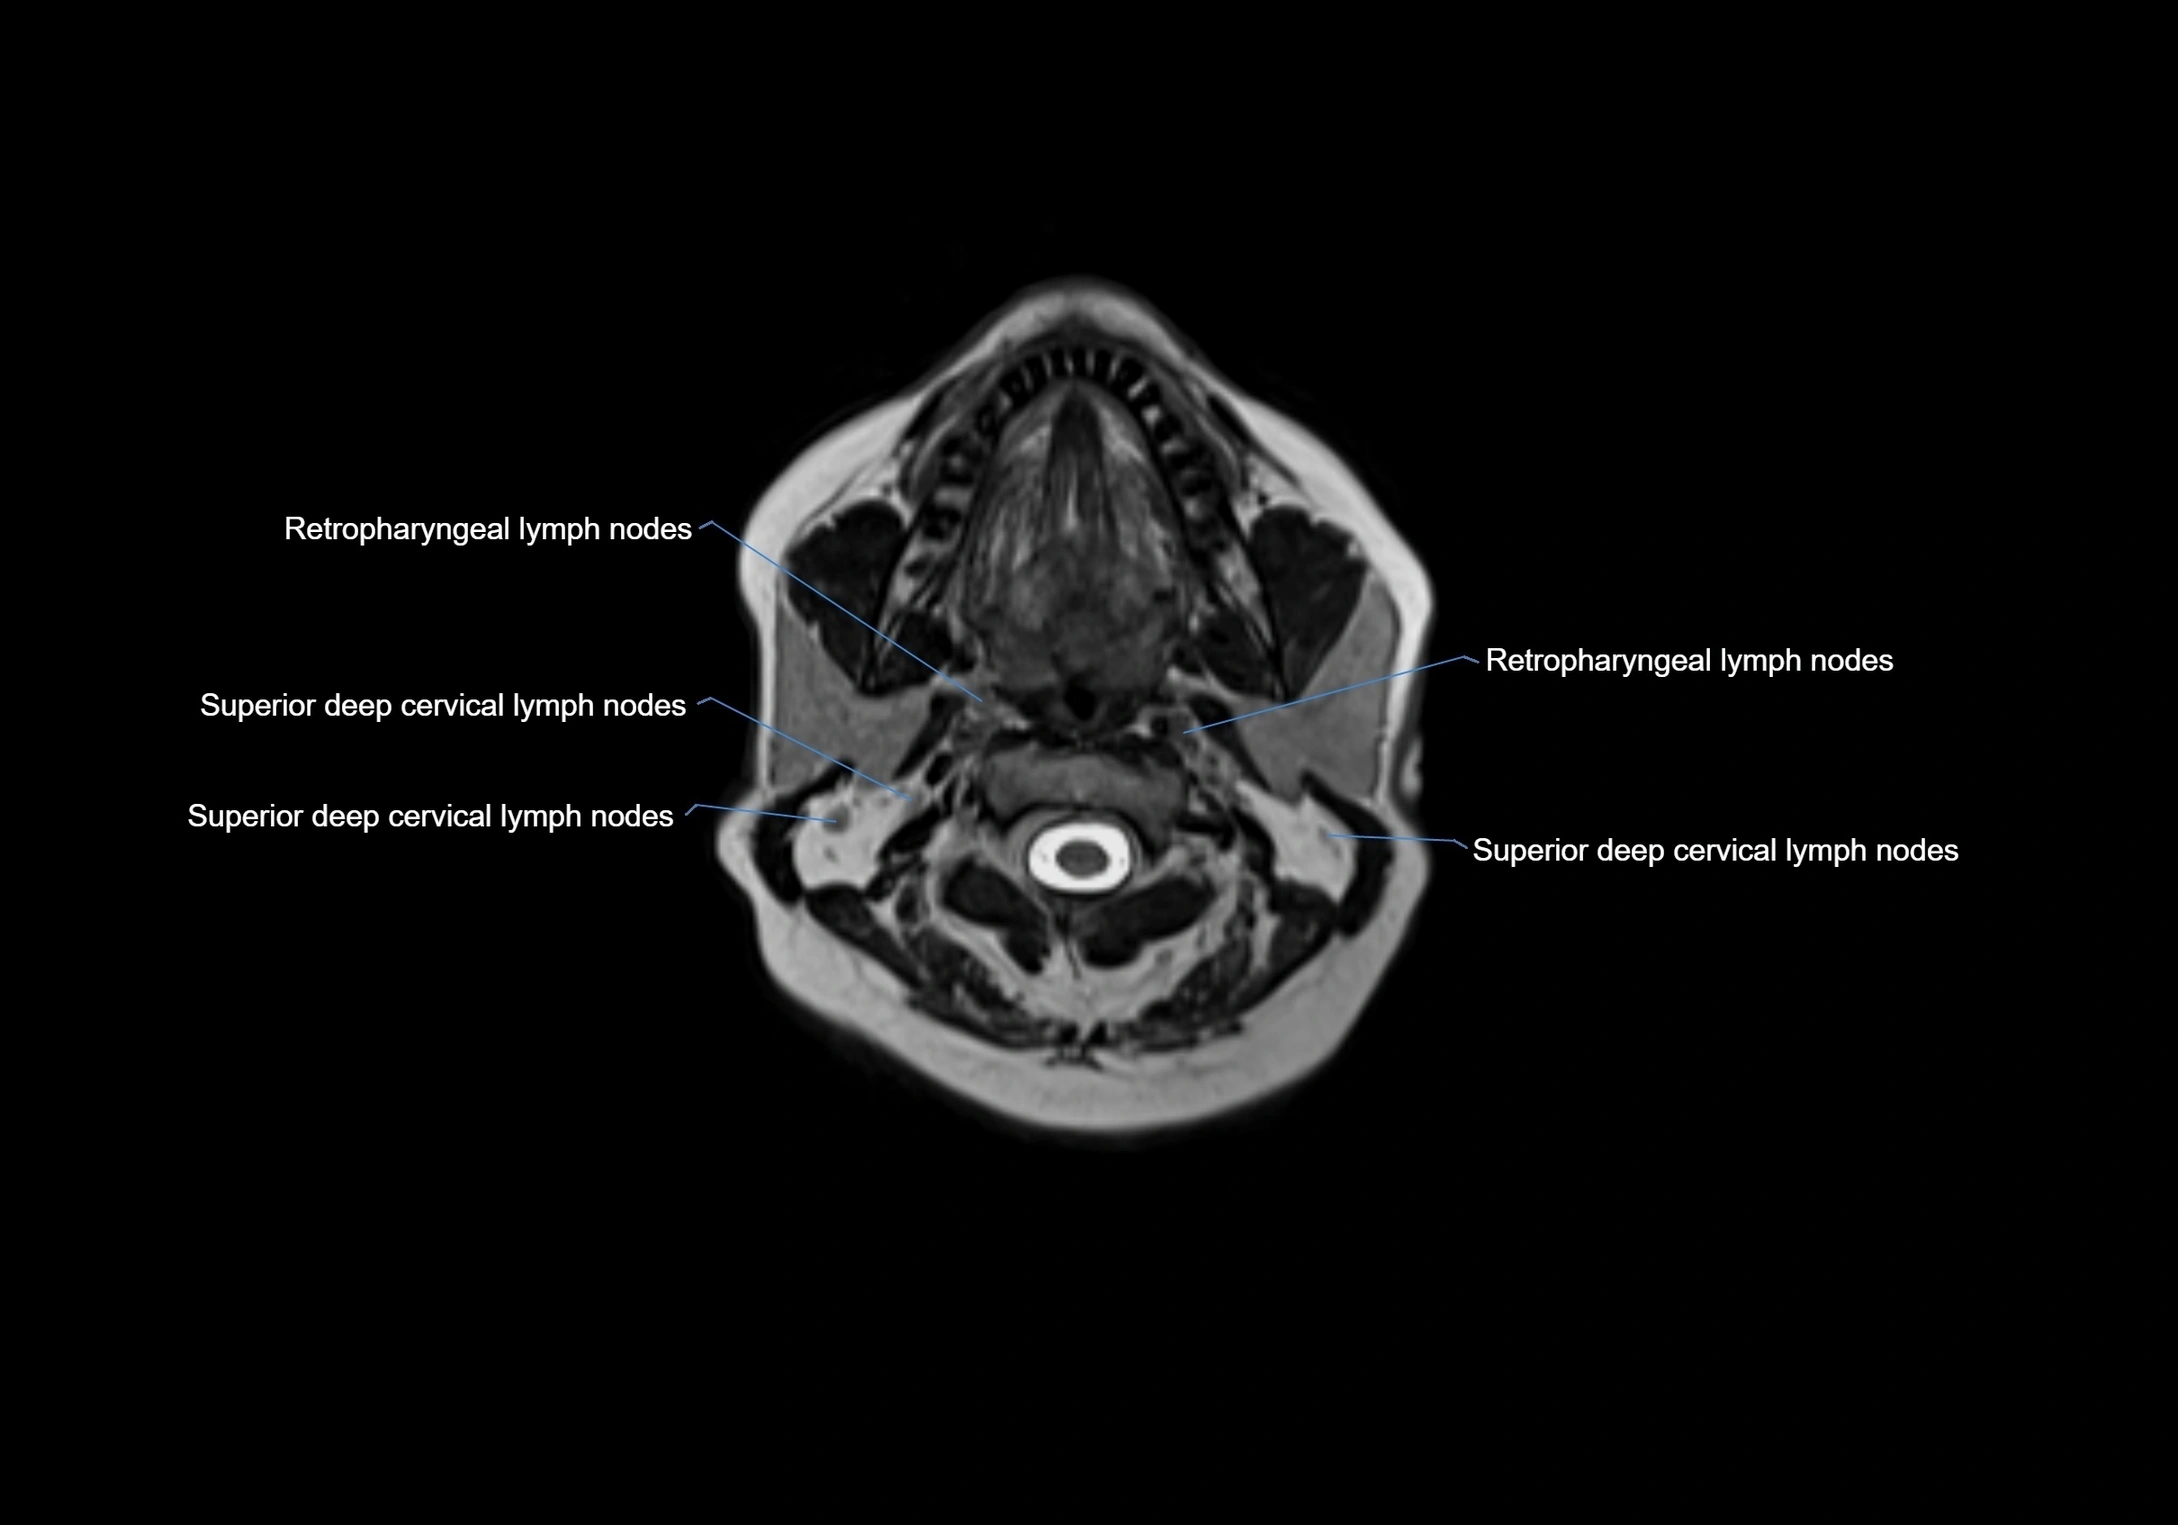

Location

• Found along primary lymph node chains, including preauricular, submandibular, parotid, and occipital regions

• Embedded in subcutaneous fat or superficial fascia, often lateral or posterior to primary nodes

• Variable in number; may occur unilaterally or bilaterally, depending on individual anatomy

MRI images